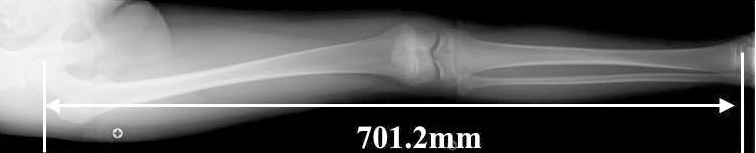

Providing super high accuracy measurements

SLOT Advance collimates the X-ray beam, so that it only exposes a narrow central slit field without distortion caused by oblique rays. These central slit images are captured using the SONIALVISION's super-high resolution Flat Panel Detector (FPD) by moving it in parallel with the X-ray tube. These successive images are then automatically reconstructed to create one long image in SONIALVISION G4's digital imaging unit (DR-300).

Therefore, this enables very high accuracy measurements without distortion, even with a very simple workflow.

Accurate measurements

CR stitching